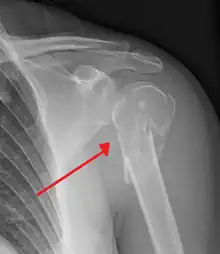

Proximal humerus fracture

A displaced supracondylar fracture in a child